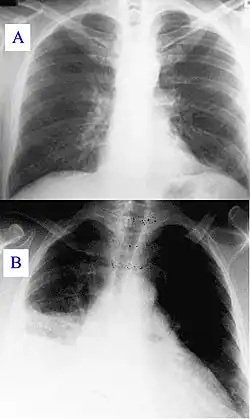

Zdjęcie rentgenowskie klatki piersiowej

Zdjęcie rentgenowskie klatki piersiowej, radiogram klatki piersiowej, rtg klatki piersiowej (ang. chest X-ray) – badanie radiologiczne polegające na przepuszczeniu przez klatkę piersiową kontrolowanych dawek promieni rentgenowskich, rzutowanych na prostopadłą płaszczyznę z detektorem tych promieni. Rtg klatki piersiowej, tzw. zdjęcie przeglądowe, jest najczęściej wykonywanym badaniem rentgenowskim w medycynie i powinno być pierwszym diagnostycznym badaniem u chorych z objawami choroby płuc. Badanie stanowi około 20% wszystkich badań obrazowych[1]. Jest stosunkowo szybkie i łatwe do wykonania, niedrogie i charakteryzuje się niskim promieniowaniem (około 0,01–0,03 skutecznej dawki mSv dla ekspozycji p-a). Odpowiada to czasowi równoważnemu promieniowaniu tła (promieniowanie jonizujące, które pochodzi z naturalnych źródeł na ziemi, z kosmosu i z wnętrza człowieka) wynoszącemu około 10 dni[2][3][4].

Badanie RTG klatki piersiowej wykonuje się w celu wykrycia lub wykluczenia chorób układu oddechowego, narządów śródpiersia, opłucnej, oraz w ograniczonym zakresie szkieletu kostnego klatki piersiowej i serca. Wyniki badań radiologicznych klatki piersiowej dostarczają wielu wyników, które w dużym stopniu wpływają na decyzje diagnostyczne i terapeutyczne[3].

- różnicuje odmę, niedodmę, płyn w opłucnej

- pozwala wykryć zmiany w miąższu płuc (zapalne i nowotworowe)

- odma opłucnowa

- gruźlica

- zapalenie płuc